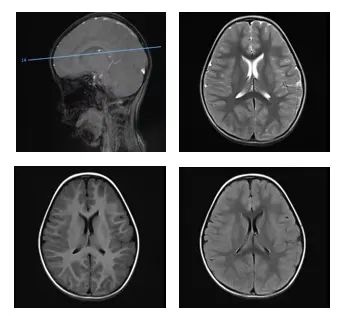

检查发现,她急性酒精中毒,出现了严重代谢性酸中毒、大脑功能受损

△检查发现,患儿出现了颅内多发病变经过治疗两天后,晓月醒了一周后,她被转入神经内科继续康复治疗近日复查时,晓月除了语速稍慢,没有其他问题“想不到,酒精擦身退烧,危害这么大!”其实,这还算幸运的用这种酒精擦身退烧,